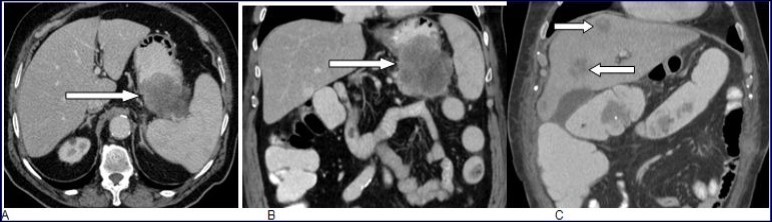

Abdominal CT scan with intravenous contrast material enhancement showed a huge mass of the gastric body, largely necrotic, infiltrating the pancreatic tail, the spleen and the left transverse colon. CT scan did not reveal any other lesion than the except gastric tumor (Figure 1. A, B).

Figure 1.A and B, Abdominal CT scan with intravenous contrast enhancement showed a huge mass of the gastric body, largely necrotic, infiltrating the pancreatic tail, the spleen and the left transverse colon. CT scan did not reveal any other lesion except the gastric tumor. C: Multiples liver metastases two months after surgical operation.

Follow-up thoracic-abdominal CT scan obtained two months after surgical operation showed liver and lung metastasis and multiple retroperitoneal lymph nodes (Figure 1, C). Palliative chemotherapy was then indicated. Unfortunately, the patient's condition deteriorated rapidly and he expired three months later.